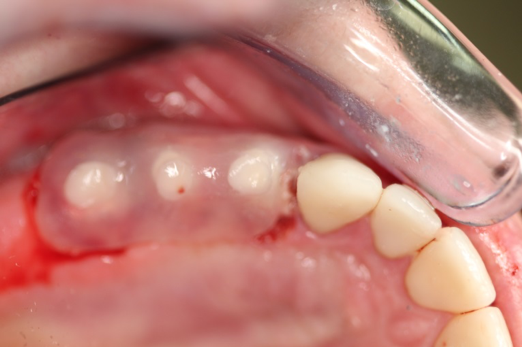

Fig 6. After splint removal (12 weeks postoperatively).

Figure 6

Fig 7. 12 weeks postoperatively.

Figure 7

Figure 3 through Figure 5 show the fitting of a one-piece multiple splint using a light-cured acrylic, along with flowable composite to adhere the splint to the three ceramic dental implants. The splint was to remain out of occlusion, without any occlusal forces for the 12-week osseointegration period. The patient was instructed to chew on the other side of her mouth for the 12 weeks before returning to the dental practice for simple removal of the splint. Removal of the splint revealed optimum results. The soft tissues were pink, with keratinized gingival margins completely surrounding the ceramic implants and consistent with what most dentists observe with the periodontium around periodontally healthy natural teeth (Figure 6 and Figure 7).